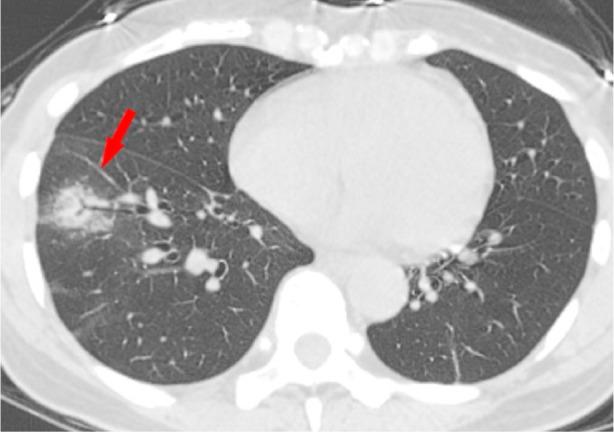

In December 2019, an outbreak of severe acute respiratory syndrome coronavirus 2 infection occurred in Wuhan, Hubei Province, China, and spread across China and beyond. On February 12, 2020, the World Health Organization officially named the disease caused by the novel coronavirus as coronavirus disease 2019 (COVID-19). Because most patients infected with COVID-19 had pneumonia and characteristic CT imaging patterns, radiologic examinations have become vital in early diagnosis and the assessment of disease course. To date, CT findings have been recommended as major evidence for clinical diagnosis of COVID-19 in Hubei, China. This review focuses on the etiology, epidemiology, and clinical symptoms of COVID-19 while highlighting the role of chest CT in prevention and disease control.

2019 年 12 月,中国湖北省武汉市发生了严重急性呼吸综合征冠状病毒 2 型感染的爆发,并在中国乃至全球蔓延。2020 年 2 月 12 日,世界卫生组织正式将由新型冠状病毒引起的疾病命名为 2019 冠状病毒病(COVID-19)。由于大多数感染 COVID-19 的患者都患有肺炎和特征性的 CT 影像学模式,放射学检查在早期诊断和疾病过程评估中变得至关重要。迄今为止,CT 检查结果已被推荐为中国湖北省 COVID-19 临床诊断的主要依据。本综述重点介绍了 COVID-19 的病因、流行病学和临床症状,同时强调了胸部 CT 在预防和疾病控制中的作用。